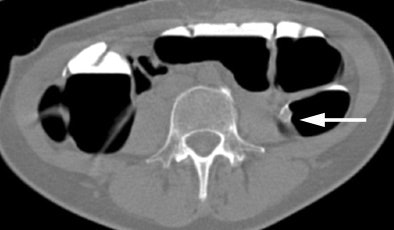

| Axial CT colonographic (VC) image in the prone acquisition shows polyp (arrow) within descending colon. Note homogeneous tagging of the feces throughout the colon. Image courtesy of Dr. Riccardo Iannaccone. |

According to the latest results in 180 patients, conventional colonoscopy identified two carcinomas and 76 polyps in 42 patients; the remaining 138 patients showed no abnormality. Virtual colonoscopy yielded an average per-polyp sensitivity of 48.6% -- 92% for polyps 8 mm or larger.